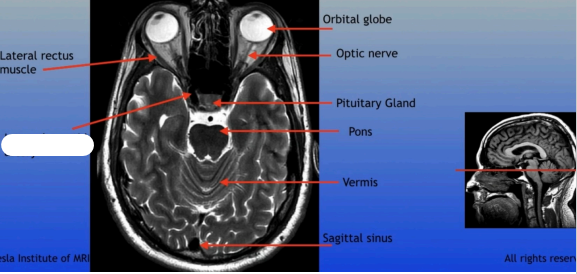

Lateral Rectus Muscle

Internal Carotid Artery

Orbital Globe

Optic Nerve

Pituitary Gland

Pons

Vermis

Sagittal Sinus